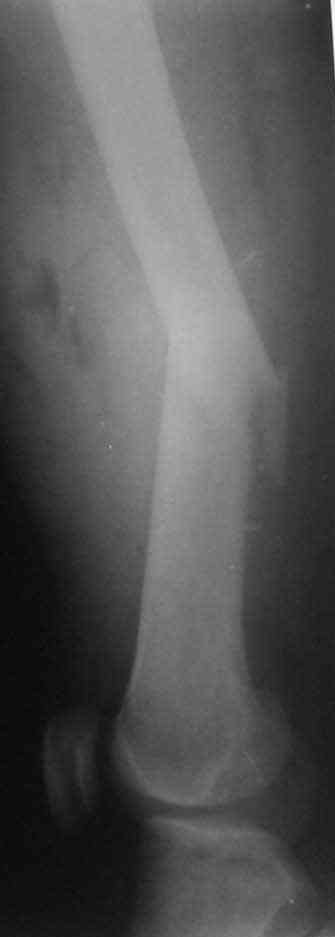

В приложении пример огнестрельного ранения бедра, оперированного на 2 сутки после ранения.

Штифтование было выполнено только на вторые сутки по причине задержки перевода из другого госпиталя, АБ профилактика была начата в другом учреждении, с момента госпитализации пациента к ним. Входное пулевое отверстие и зона введения штифта зажили первичным натяжением.

В конце 90-ых попалось несколько статей по nail exchange procedures in treatment of posttraumatic osteitis и решился попробовать на огнестрельных переломах, которые до этого лечил по полной схеме:расширенный дебрайдмент+ внешняя фиксации+промывные системы с антибиотиками и без антибиотиков в промывной среде. Всё заканчивалось длительной госпитализацией, плохими функциональными результатами( страдала функция колена), необходимостью повторной хирургией - отсроченная внутренняя фиксация переломов, длительной реабилитацией. На гвоздях процесс пошел лучше: остеомиэлитов не было и больные мобилизовывались быстрее.

Единственно что наблюдал - замедленная консолидация, судя по серийным Рг граммам. В приведенном случае прии вялом мозолееобразовании сделал ошибку, решившись динамизировать гвоздь - перелом сросся со значительным укорочением бедра - повторная хирургия по удлинению бедра и проксимальным запиранием, больной мобилизован и вполне доволен(кстати заметить больной с ВИЧ инфекцией - изначально скомпрометированный иммунитет и несмотря на это, всё прошло без костной и мягкотканной инфекции.